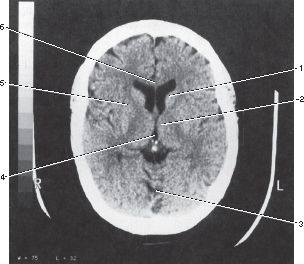

4

3rd ventricle

3

Vermis of cerebellum